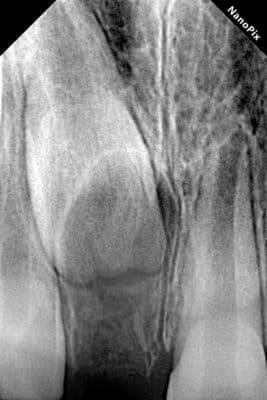

Дівчинка 7 років, перше вересня, гойдалка… Вивих постійного зуба: якщо в такій ситуації зволікати, дитина може втрати постійний зуб назавжди. Батькам порекомендували нас і пацієнти одразу приїхали. Через складність і травматичність процедур вирішено проводити лікування в анестезіологічному супроводі. Зуб поставлений на місце (репонований), проведена хірургічна обробка і ушивання рани губи. Останнє фото через рік після травми: зуб на місці і корінь продовжує розвиватись, губа повністю загоїлась